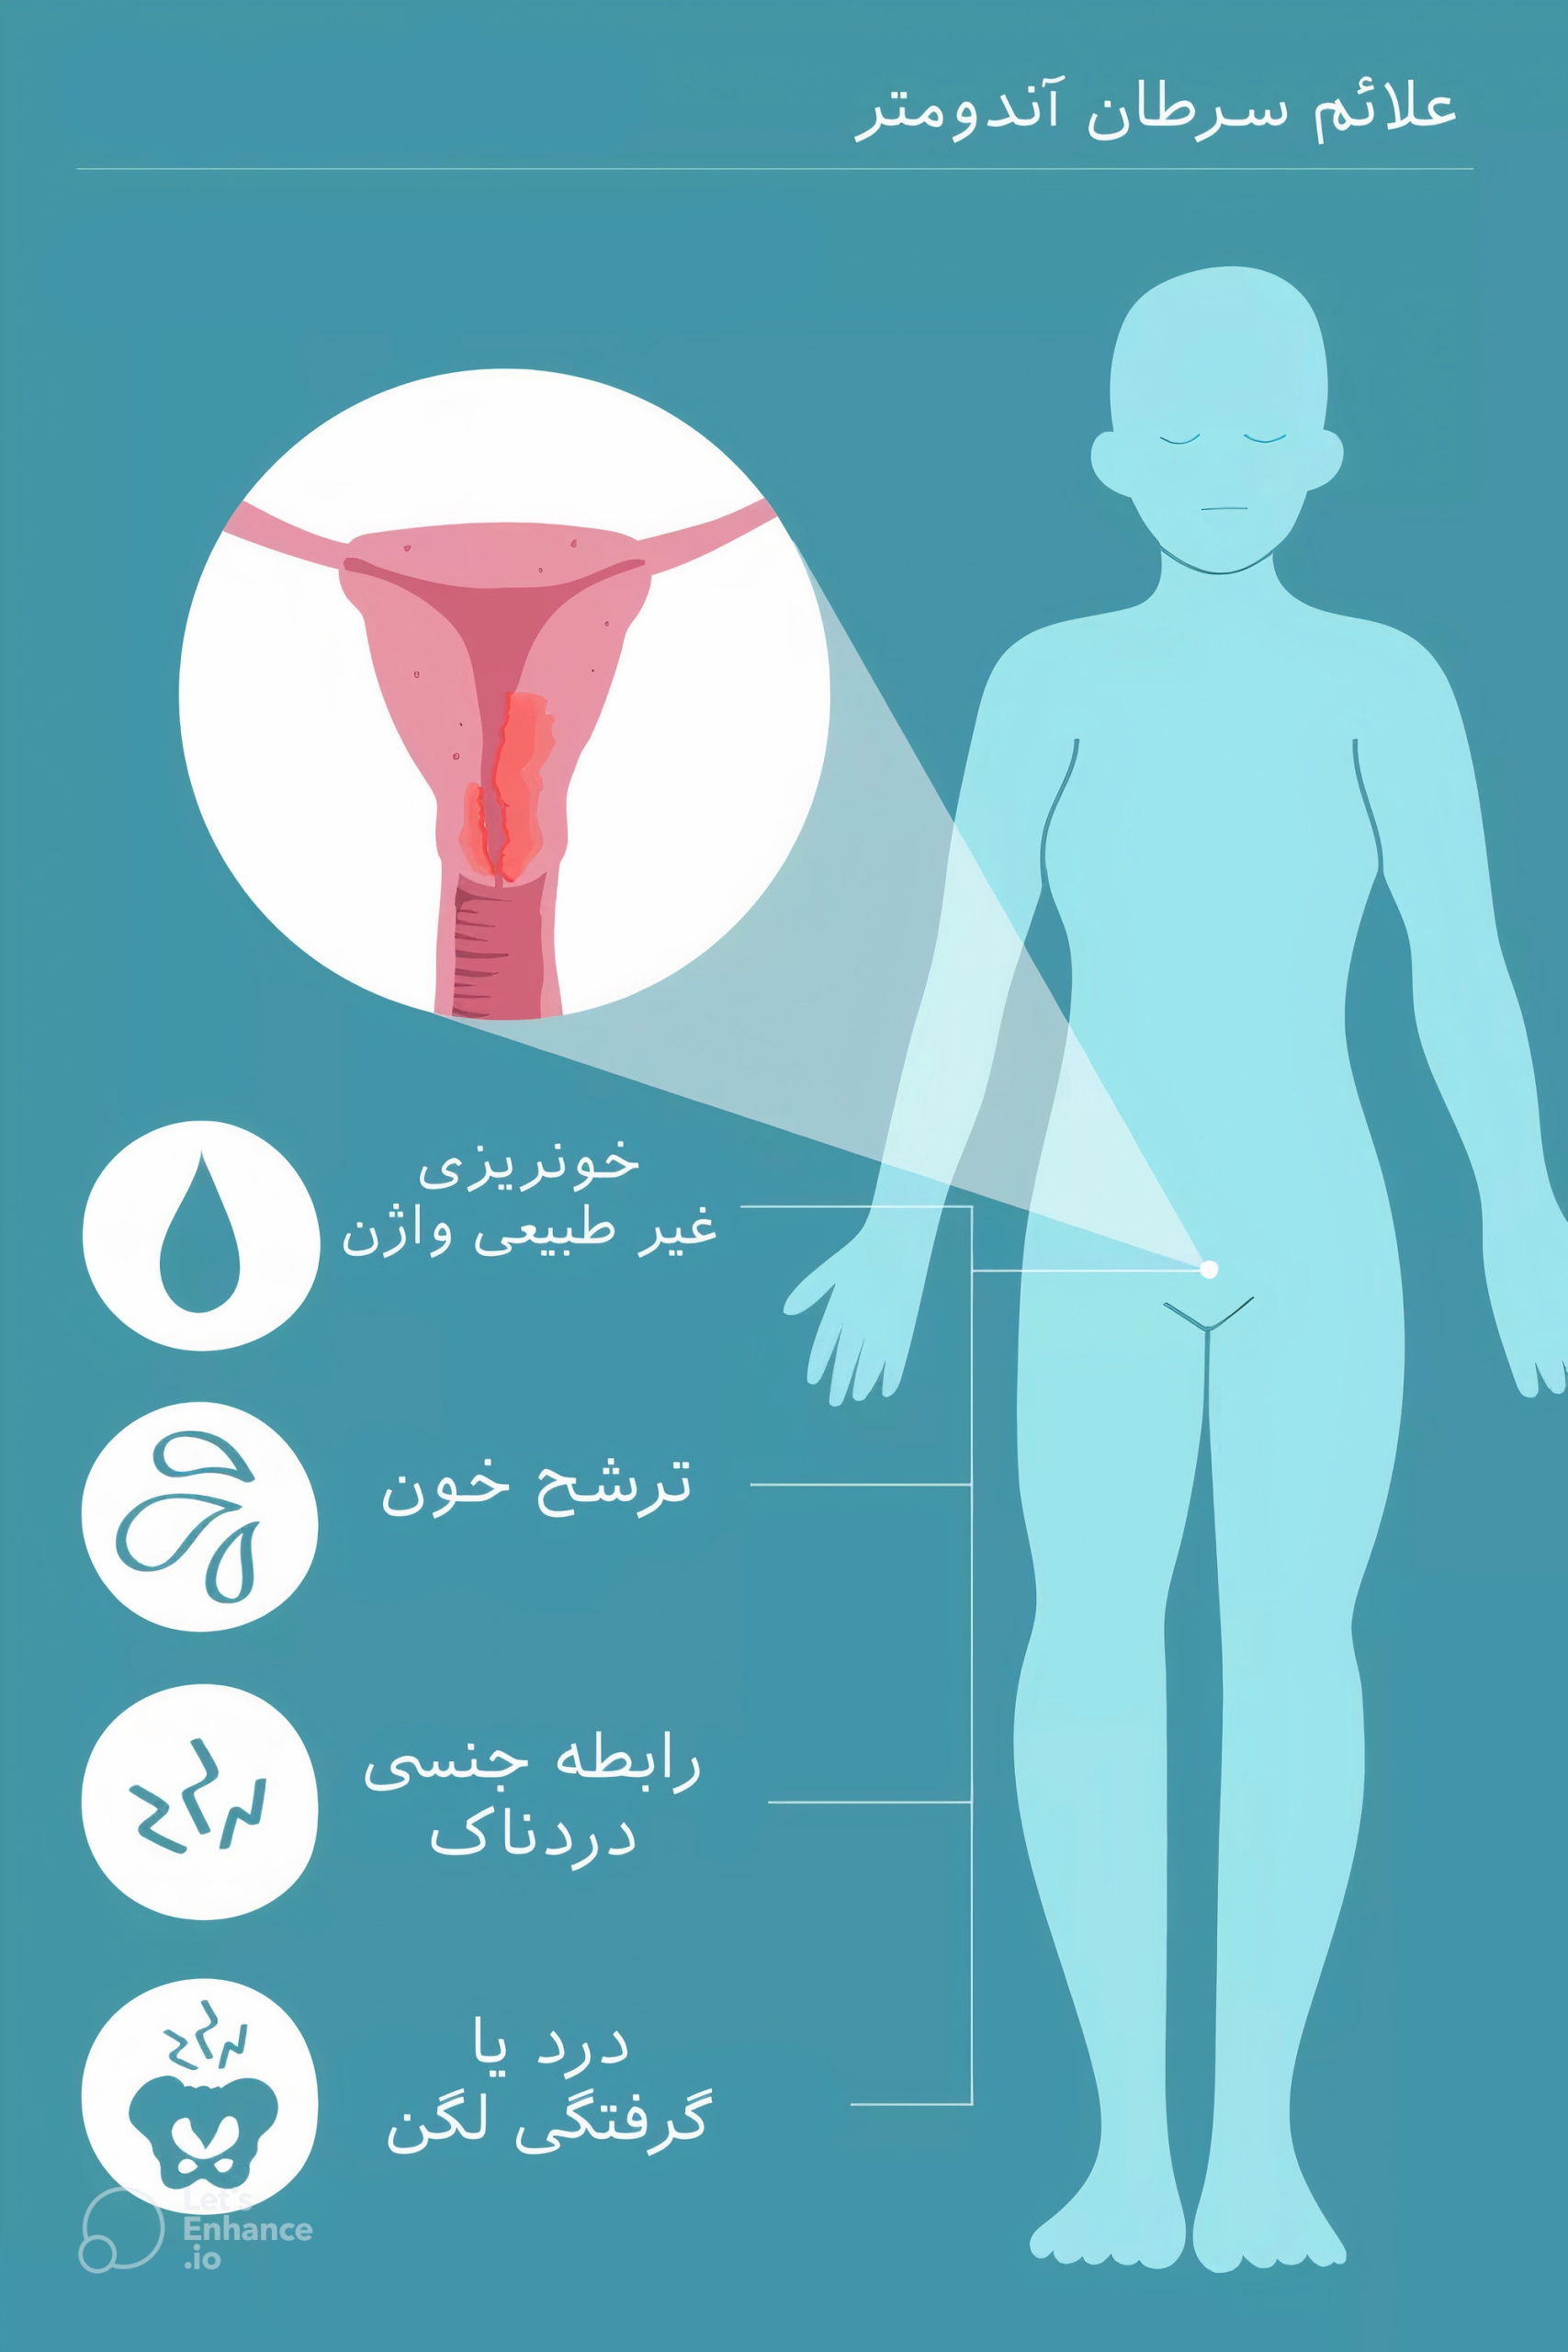

علائم و نشانههای عدم تخمک گذاری چیست؟

آگاهی از علائم کلی تخمک گذاری و پیگیری چرخههای قاعدگی میتواند به شما در مورد علائم و نشانههای نبود تخمک گذاری، هشدار دهد. مهم است که به یاد داشته باشید که پریود شدن لزوماً به معنای تخمک گذاری شما نیست. علائم و نشانههای عدم تخمک گذاری میتواند شامل موارد زیر باشد:

- داشتن قاعدگی های نامنظم: اگر مدت زمان بین پریودهای شما مدام در حال تغییر باشد، یک دوره نامنظم در نظر گرفته میشود. متوسط چرخه قاعدگی 28 روز است، اما میتواند چند روز کوتاهتر یا طولانیتر از آن باشد.

- پریودهای بسیار سنگین یا سبک: پریود سنگین با از دست دادن بیش از 16 قاشق چای خوری (80 میلی لیتر) خون در طول قاعدگی و/یا داشتن دورهای که بیش از هفت روط طول میکشد تعریف میشود. از دست دادن خون کمتر از چهار قاشق چایخوری (20 میلی لیتر) در طول قاعدگی یک دوره سبک در نظر گرفته میشود.

- فقدان پریود (آمنوره): از دست دادن یک یا چند دوره بدون بارداری، میتواند نشانه عدم تخمکگذاری باشد.

- فقدان مخاط دهانه رحم: درست قبل و در حین تخمک گذاری، معمولاً بیشترین ترشحات واژن به نام مخاط دهانه رحم را دارید که معمولا شبیه سفیده تخم مرغ خام است. اگر این ترشح را ندارید، ممکن است دچار عدم تخمک گذاری شده باشید.

- داشتن دمای پایه بدن نامنظم: دمای پایه بدن شما زمانی است که به طور کامل در حالت استراحت هستید. معمولاً بعد از بیدار شدن از خواب و قبل از انجام هر نوع حرکت یا فعالیت بدنی مصرف می شود. تخمک گذاری میتواند باعث افزایش جزئی در دمای پایه بدن شما شود.